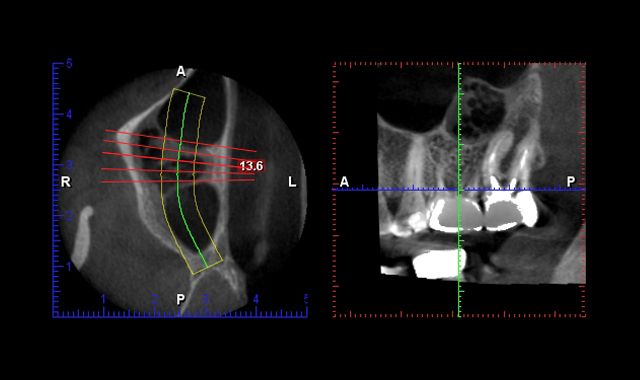

Having an intraoral scanner and a cone beam is the perfect marriage. Both are completely independent of each other. The scanner focuses on teeth and tissue and the cone beam addresses the bony architecture. When the STL files are joined in the lab, there is complete harmony. Like a great marriage, they make each other better. From my understanding and speaking with different vendors, one can take a DICOM file obtained from the CBCT, convert it, make a virtual model, 3D printed model and fabricate a crown. So, in theory, you could prep a tooth and have an edentulous area. Plan the implant and make the crown or partial all at the same time. And then there are times we just need to take an intraoral scan and make a crown inlay or onlay.